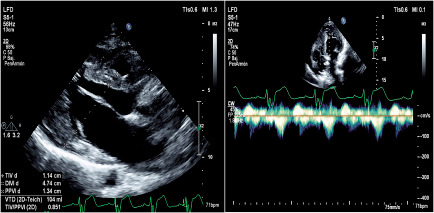

Hypertrophic cardiomyopathy has a different presentation spectrum, including left ventricular outflow tract obstruction. The most common phenotype is the asymmetric septal variant, with the mid-apical variant being rare. On the other hand, there are specific mutations associated with hypertrophic cardiomyopathy, with the Filamin C variant being an unusual condition in these patients. Therefore, we present the case of a 23-year-old male patient with a diagnosis of hypertrophic cardiomyopathy in whom a Filamin C variant was documented. Given the inadequate response and persistence of symptoms to medical management, a myectomy procedure was performed with a transapical approach, with subsequent improvement in clinical symptoms and outflow tract obstruction. This case illustrates a rare variant with a surgical approach different from the conventional transaortic approach, with marked improvement in symptoms.